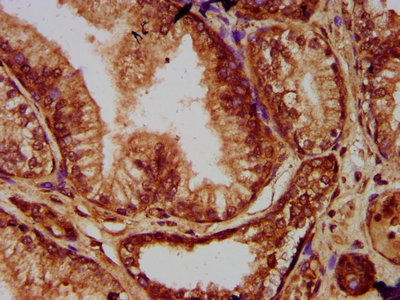

IHC (Immunohistochemistry)

(IHC image of AAA234842 diluted at 1:200 and staining in paraffin-embedded human prostate tissue performed on a Leica BondTM system. After dewaxing and hydration, antigen retrieval was mediated by high pressure in a citrate buffer (pH 6.0). Section was blocked with 10% normal goat serum 30min at RT. Then primary antibody (1% BSA) was incubated at 4 degree C overnight. The primary is detected by a biotinylated secondary antibody and visualized using an HRP conjugated SP system.)